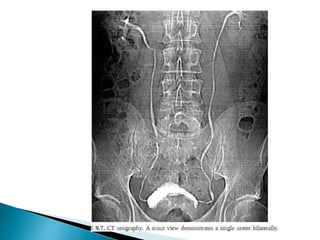

 CT is the preferred imaging due to better spatial resolution

and sensitivity to vascular calcifications and renal stones.

NECT Calculi /vascular calcification

Arterial phase Vascular supply

Delayed image Collecting system